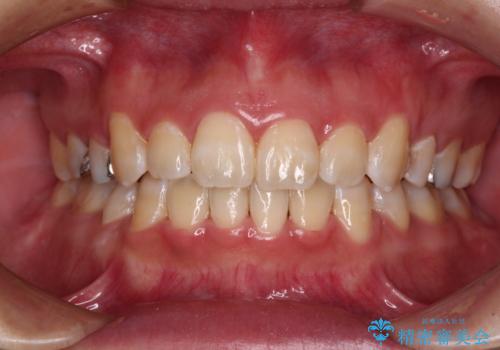

- 口元のデコボコと深い咬み合わせ(ディープバイト)を気にして来院された患者様です。

インビザラインによる上下歯列の拡大と、IPR(歯と歯の間を削る)にるスペースの獲得により、口元のデコボコとディープバイトを改善することとしました。